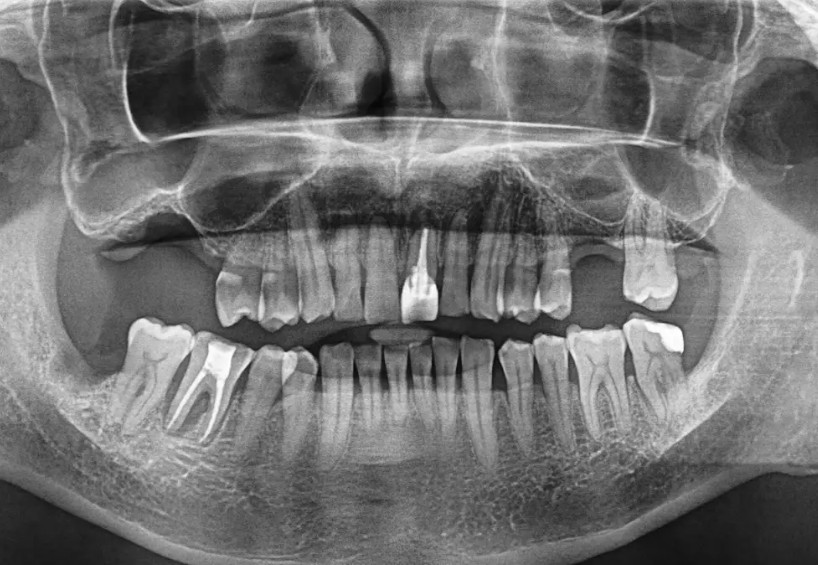

画像所見

デンタルX線およびCTで、根尖部に透過像(黒い影)を認め、根尖周囲骨が大きく吸収されていることが確認されました。根の破折はなく、根管形態は保存可能。

また、歯周骨の垂直性吸収(根の側面に沿った骨の欠損)もあり、根尖部から歯周ポケットへの感染経路が形成されていました。

このような“エンド・ペリオ連続病変”は、抜歯適応の最終段階とされる重症状態です。

診断名:感染根管治療後の再発性根尖性歯周炎を伴う重度歯周炎(エンド・ペリオ病変)保存の可能性は低いが、

治療終了時には、レントゲン上で骨の再生が明瞭に確認されました。

治療終了時には、レントゲン上で骨の再生が明瞭に確認されました。患者さん自身も「噛めるようになった」「違和感がない」と実感され、何より“抜かずに済んだ”ことへの喜びが大きかったそうです。

本症例は、抜歯適応レベルの重度エンド・ペリオ病変に対して、感染源の徹底除去と再生療法の併用で機能回復を得た貴重なケースです。根管治療単独では治癒が困難な場合でも、歯周再生療法を組み合わせることで骨の再生を促し、残存歯の保存をおこなえる可能性があります。